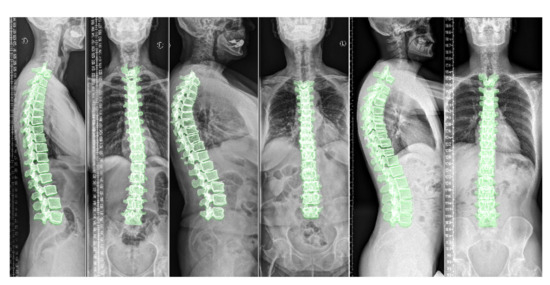

To appreciate the difference of spine posture in the standing and lying down positions, we illustrate the two cases we used in this experiment in Figure 12. The spine postures reconstructed from radiographs in upright standing position are depicted on the left and the ones from CT are depicted on the right side of the figure.

Training the model with a dataset containing more scans with lumbar vertebrae, could improve the model performance in the lumbar region. As depicted in Figure 12, we compared the standing and lying down spine postures of two patients. Acquiring more annotated pairs of CT scans and radiographs of the same patient could enrich the results and provide more data for validation. We use a relatively large-scale dataset for training our model. Although the size and anatomical variations in patients helps the model learn the shapes and deformations, we believe that data augmentation by adding a small randomness to the projection angle in the simulated radiographs could teach the model this randomness in clinical radiographs.

Figure 12. Comparing 3D reconstructions of the standing spinal posture from clinical radiographs (left, green) to the spinal posture of the same patient in lying-down position from CT imaging (right, yellow) in two different patients. In the upright-standing posture the spine is under natural weight bearing, which leads to a different spine curvature.